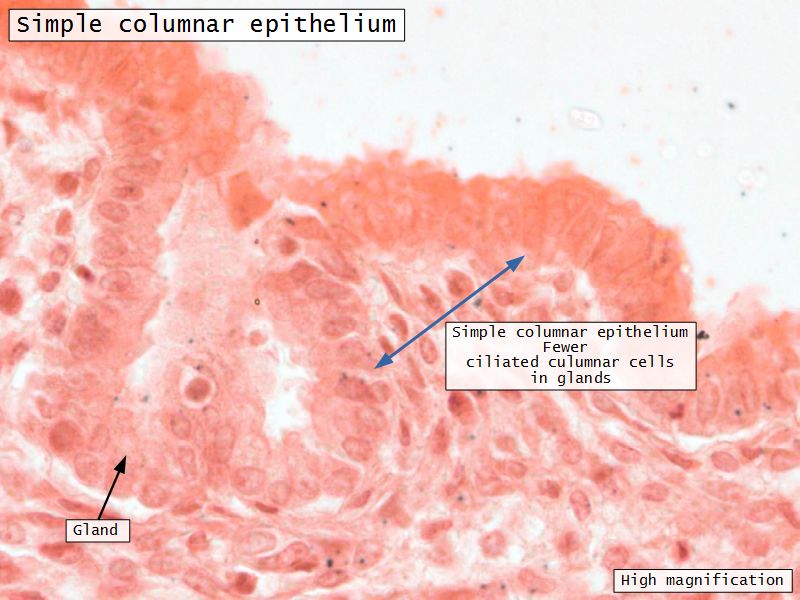

Endometrium

- Epithelium

- Simple columnar

- Two cell types

- Secretory

- Ciliated

- Glands

- Similar but fewer ciliated

Endometrial glands

- Extend through basal layer

- Source of cells to reestablish endometrium